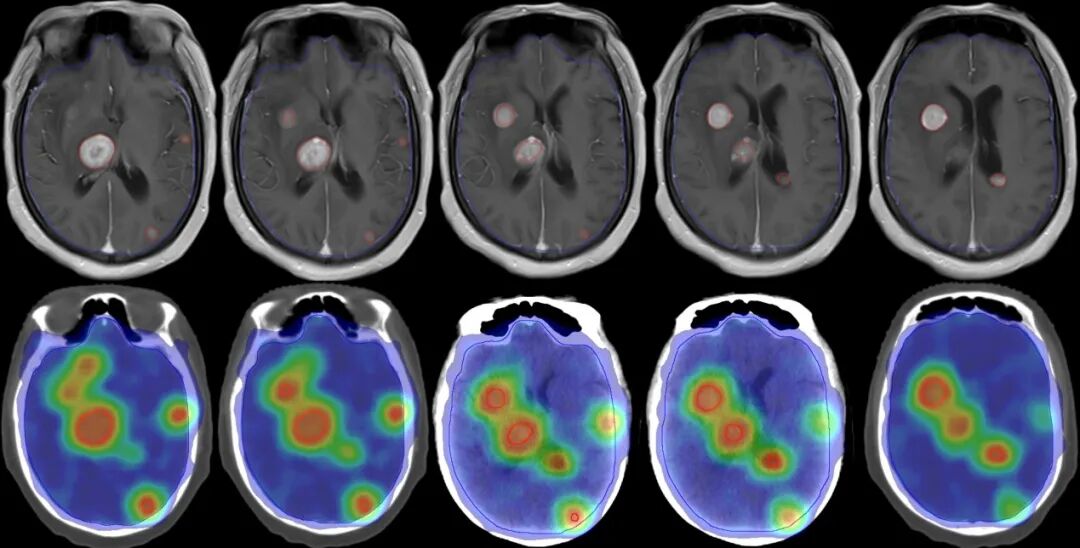

【學科風采】乳腺癌患者千里求醫(yī),成功治療多發(fā)腦轉移瘤、脊髓轉移、腦膜轉移、椎管內多發(fā)轉移結節(jié)、肺炎及肺門轉移患者